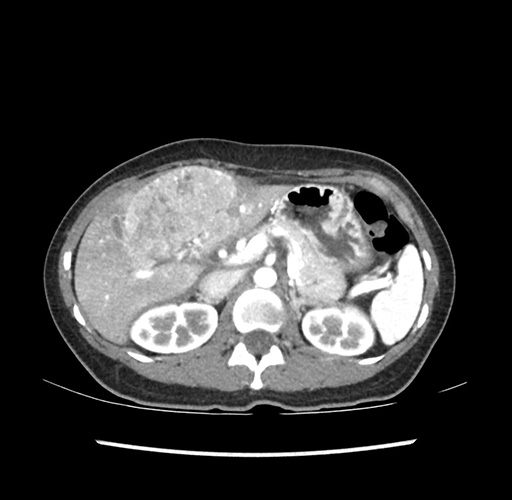

Imaging Analysis

Look through the patient's CT scan to identify any areas of concern for the necessary procedure.

Based on your CT findings, which issue(s) would give reason for "planned slowing down moment(s)" in this case?

Considering a standard left lateral sectionectomy procedure, what step(s) of the operation would you do differently in this case ?